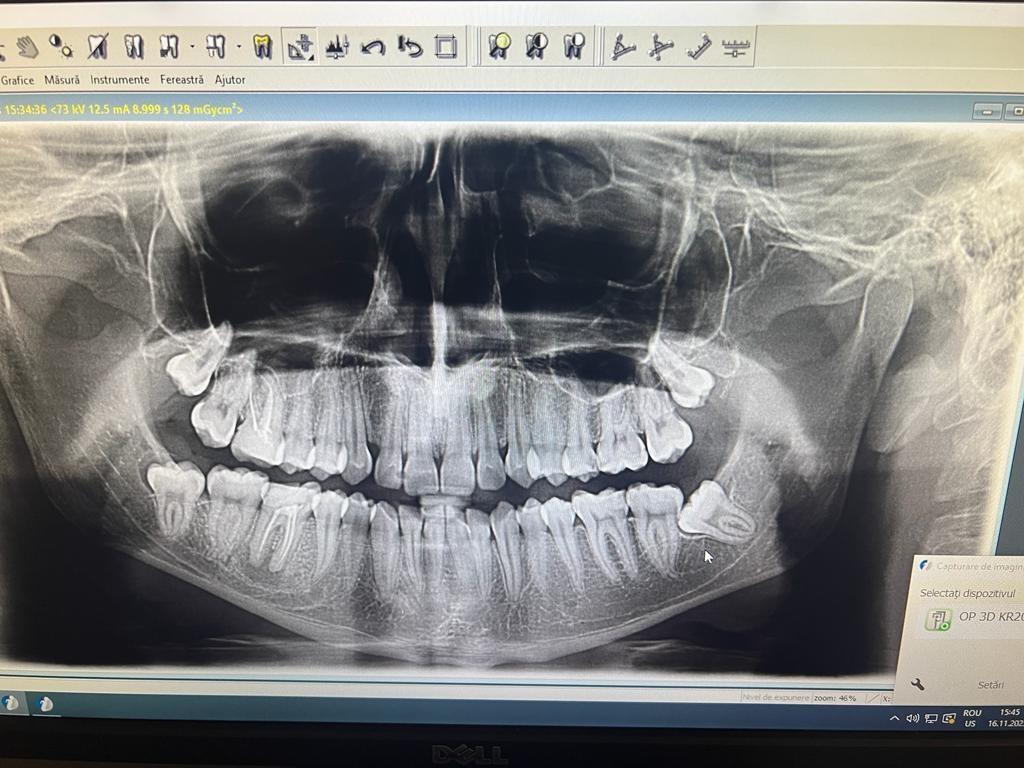

Clinica LUY ESTHETIC ART defineste parodontoza ca fiind rezultatul direct al placii dentare, care se depune pe suprafata dintilor, dar si in apropiere de marginea gingivala. Aceasta boala duce la pierderea dintilor, chiar daca ei sunt aparent sanatosi si nu prezinta carii. Edentatiile, afecteaza vorbirea, aspectul, dar si capacitatea de a mesteca.

Boala parodontala are un caracter progresiv. Pentru cazurile mai grave, recomandam tratamentul parodontal chirurgical rezectiv sau regenerativ.

O igiena bucala necorespunzatoare, fumatul, placa bacteriana si alte boli generale, permit bacteriilor sa se dezvolte in cavitatea bucala.